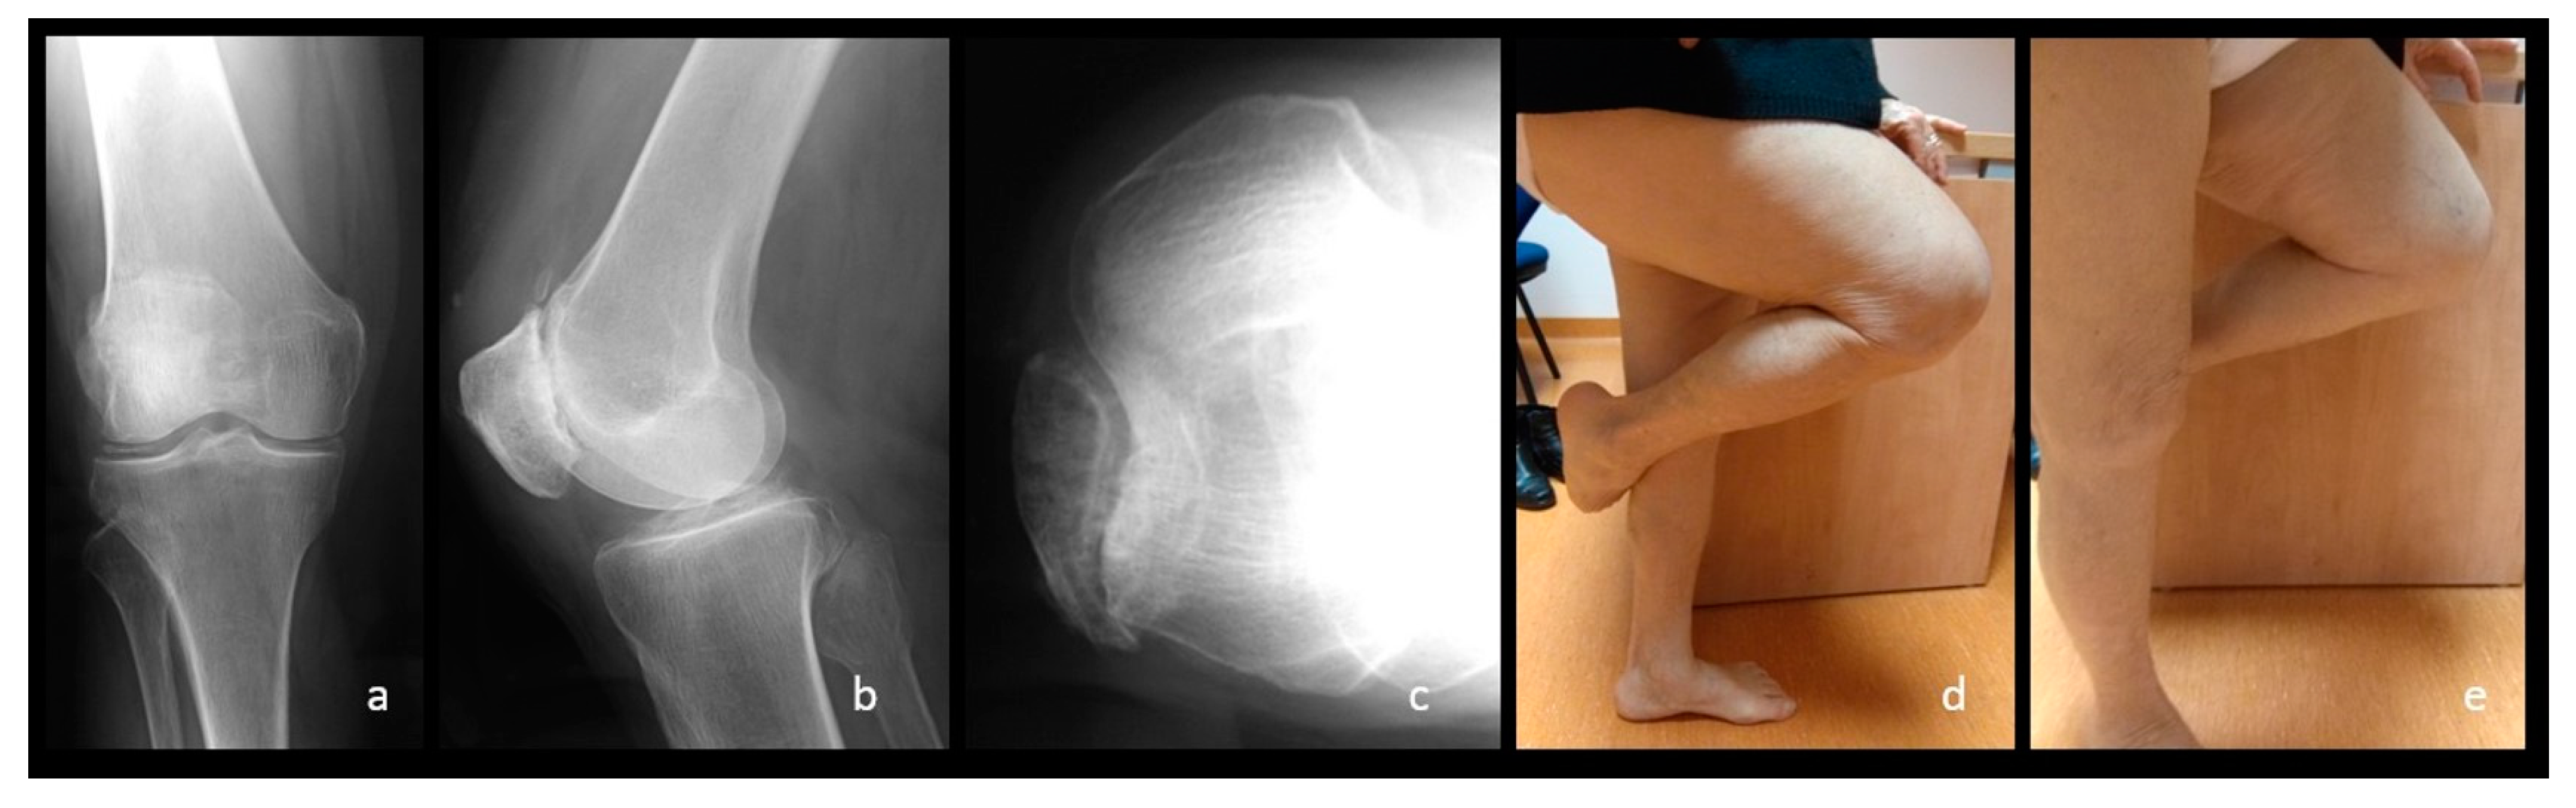

Figure 8.

Radiographical (a–c) and clinical evaluations (d,e), performed at 8 months after the surgery. Please note the good knee function as compared with the non-affected side. A comparable-to- -pre-operative radiographic stage two patella-femoral arthritis could be observed at final-follow up.